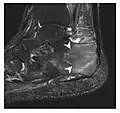

Figure 10: Calcaneal fatigue fracture in a 30-year-old male runner. Radiographs were normal (not shown). (a) Sagittal T1-weighted and (b) short tau inversion recovery images show a linear hypointensity (arrows) of calcaneal tuberosity within diffuse bone marrow edema, which appears as an ill-defined area of hyperintensity on a fluid sensitive pulse sequence (arrowheads).[1]

-

a -

b -

c

Figure 11: Stress fracture of the right radius in a 40-year-old man, a semiprofessional billiard player, with no history of trauma and complaining of pain of the right forearm for one month. (a) Anteroposterior radiograph shows medial radial cortex periosteal reaction (arrow) but no fracture line is seen. (b) Coronal reformatted CT depicts monocortical fracture line through the periosteal thickening (arrowheads). (c) Coronal T2-weighted fat-suppressed MRI shows intramedullary hyperintensity within the bone marrow (arrow) corresponding to bone marrow edema.[1]